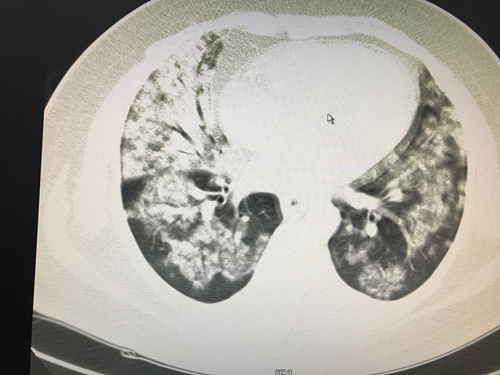

这位62岁的患者病情十分严重,下图便是当时的胸部CT截图:

这是一位重症肺炎的患者,因为严重的肺部感染已经让患者氧合难以维持,必须要通过机械通气和血管活*药性**物来维持基本的生命体征!